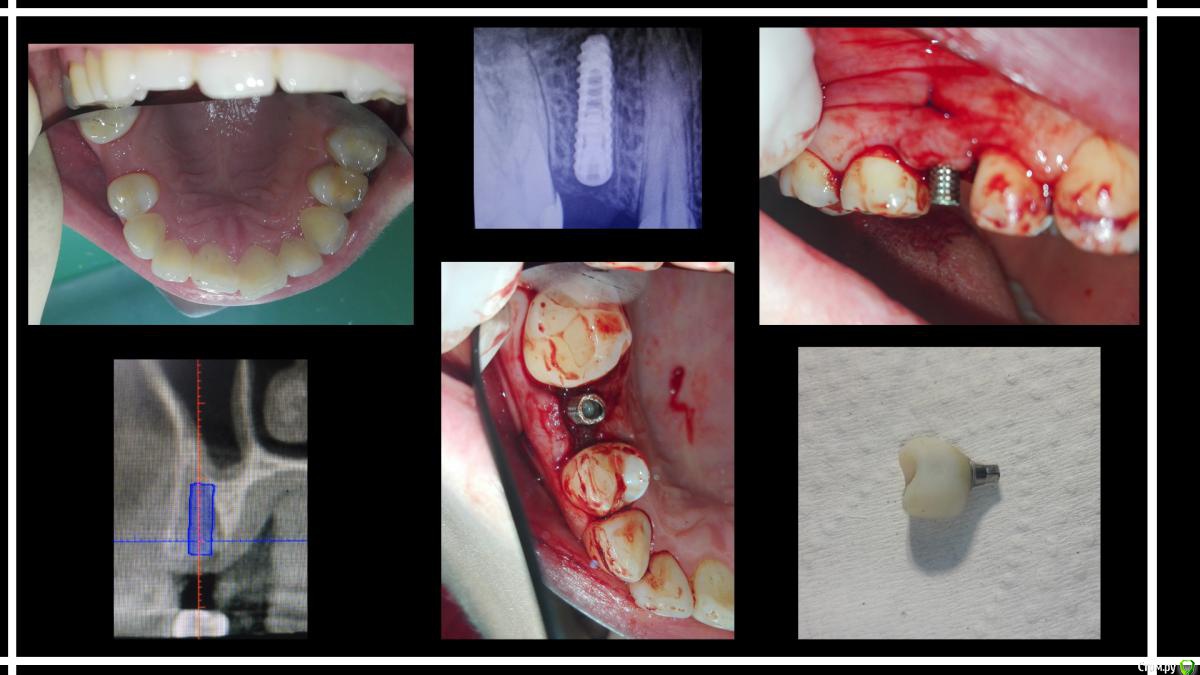

karasov Опубликовано 21 ноября, 2016 Поделиться Опубликовано 21 ноября, 2016 Удален 15, через пару месяцев osstem 3.5-10 ,тк торка не было-заглушка,ушивание. Еще 3 мес, времяшка+сст. Ну и протезирование 7 Ссылка на комментарий